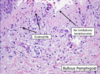

pemphigus vulgaris

40-60 yo

cutaneous erosions/oral ulcers

intact blisters are rare

Painful! Not itchy

Upper trunk and head

+nikolsky

Rx CTSD, immunosuppression

pemphigus vulgaris

40-60 yo

cutaneous erosions/oral ulcers

intact blisters are rare

Painful! Not itchy

Upper trunk and head

+nikolsky

Rx CTSD, immunosuppression